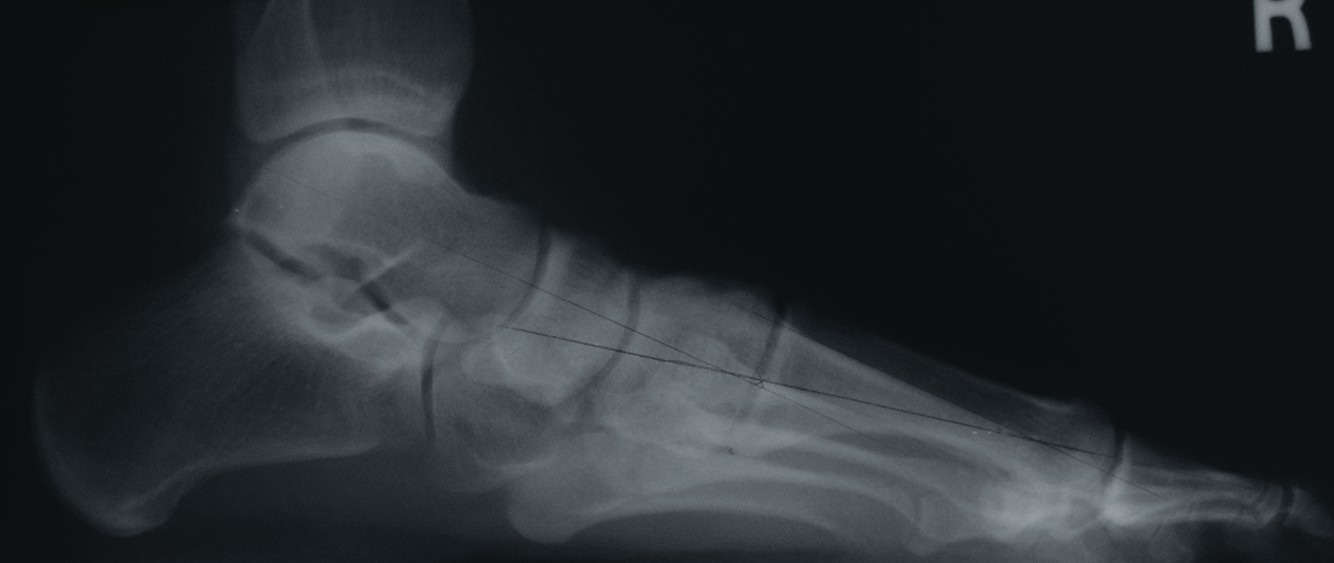

One should place the patient into a supine position and utilize a tourniquet. Evaluate post-anesthesia assessment of the first MPJ range of motion. Manually distract the first MPJ and plantarflex the first metatarsal. Dorsiflex the hallux to determine the obtainable first MPJ range of motion and evaluate for crepitus. If there is first ray hypermobility and no crepitus, one may be able to salvage the first MPJ by translating the first ray plantarly and stabilizing the medial column. Initially, surgeons should address contributing global pathology. Then proceed to the first ray and make a dorsomedial skin incision spanning the first MPJ. Retract the neurovascular structures. Make a longitudinal incision to bone, spanning the distal one-third of the first metatarsal and proximal one-half of the proximal phalanx. Evaluate the adjacent cartilage and make a critical decision to preserve or destroy the joint. It is important to realize that evaluation of cartilage quantity and quality via direct intraoperative visualization weighs heavily upon the final decision to perform a joint preservation or destructive procedure. One should strongly consider joint destructive procedures if greater than 30 percent of the dorsal portion of the first metatarsal head presents as grade III to grade IV chrondromalacia. One must independently evaluate grade III and IV chrondromalacia and osteochondral defects in the remaining 70 percent of the metatarsal head. Small cartilage lesions may yield themselves to debridement, drilling or OATS procedures whereas large cartilage defects will likely result in arthrodesis. If the joint is salvageable and one identifies first metatarsocuneiform hypermobility, perform a cheilectomy and a subsequent, sagittal Lapidus procedure. If one identifies hypermobility or posttraumatic first metatarsal angular pathology, correct it after completing the first MPJ soft tissue and osteophyte debridement. If one decides to perform arthrodesis on the joint, debride identified osteophytes, loose bodies, synovitis and scar tissue. Denude the adjacent cartilaginous surfaces to the healthy level of bleeding bone via curettage or via convex distal and concave proximal reamers. Fenestrate the adjacent bone surfaces with a 1.0- or 1.5-mm drill bit. Temporarily fixate the hallux by utilizing two K-wires in the desired position. The position should be approximately 20 to 30 degrees dorsiflexed in relation to the first metatarsal declination; abducted and parallel to the second digit; and with the nail void of frontal plane varus or valgus rotation. Obtain an AP radiograph to evaluate the bony apposition and alignment of the proposed first MPJ arthrodesis. Also obtain a lateral radiograph with the foot loaded in order to evaluate the hallux and its relationship to the first ray. After obtaining the desired position, utilize two fully threaded (3.5 or 4.0) crossing cortical screws for permanent fixation. Place the first screw from proximal medial to distal lateral and place the second screw from distal medial to proximal lateral across the first MPJ. Ensure the screws do not cross at the level of the joint. Use a 3.5-mm burr to create a dell in the cortical bone where the head of the screws engage the bone as Manloli and Hansen have described.48 After obtaining rigid internal fixation across the first MPJ, utilize a shear strain autograft (harvested via a percutaneous calcaneal grafting technique) at the arthrodesis site.57 Place the autograft in two troughs created by the 3.5-mm burr at the arthrodesis site. Use a bone mallet and tamp to provide a press fit.58